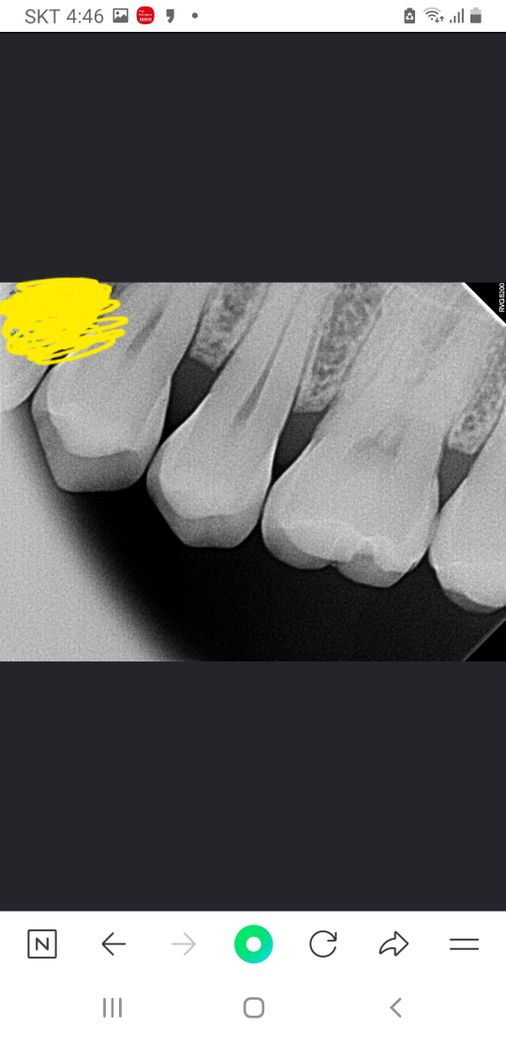

치근단사진좀 살펴봐 주세요. (치식과 충치여부)

치아 치근단사진 에서 보이는 치아가 몇번 (치식)

인지요? 충치나 파절이 있는지 궁금합니다.

겉으로는 검은색이 보이는데 오른쪽 위 뒤에서 세번째.

치근단사진상 보이는 것이 있는지요?

엑스레이 상으로는 치아 사이는 크게 충치가 잇어 보이진 않습니다. 사진에서 보이는 큰 어금니의 씹는면은 약간 깨진부위가 잇는거 같습니다.

교익 사진으로만 봤을 경우에는 큰 충치가 보이지는 않습니다.

하지만 육안상으로 보이는 충치가 있을 수 있기 때문에 정확한 확인을 위해서는 치과에서 진료를 받아 보는 것이 좋습니다.

25번 치아이고 방사선사진상 충치나 파절은 보이지 않습니다

육안으로 보이는 검은색 선은 초기충치일 가능성이 있습니다